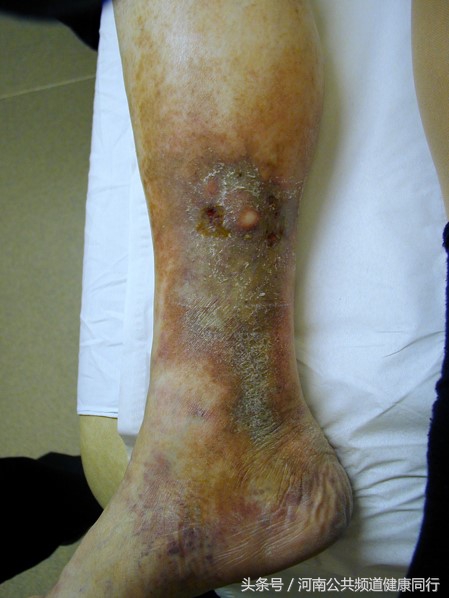

有很多种不同的表现,从轻微到严重:A,正常的下肢,B,毛细血管扩张或网状静脉,最轻。C,直径大于3mm的曲张静脉,D,下肢水肿, E,色素沉着或湿疹,F,脂质硬化,G,愈合的溃疡 ,H,未愈合的溃疡,最严重。

脂质硬化就是是皮下脂肪的炎症,会有色素沉着,颜色改变,触摸皮肤变硬。